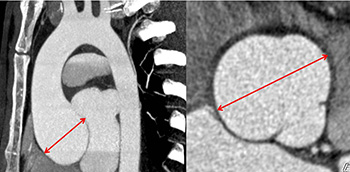

La raíz de aorta es la parte más proximal de la aorta. Se extiende desde el anillo aórtico hasta la unión sinotubular. Funciona como una estructura de soporte para la válvula aórtica, da origen a las arterias coronarias y se prolonga distalmente con la aorta...